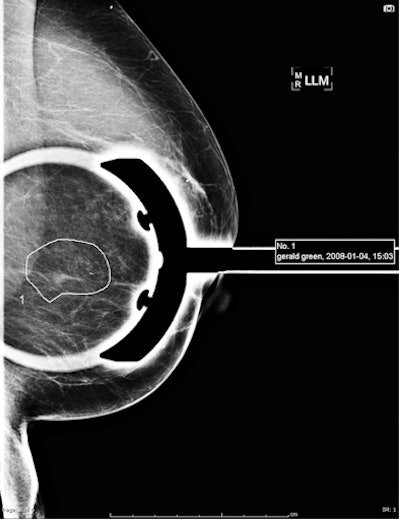

![]() |

| The mammogram image (above) shows the detected tumor in the left breast, but the BSGI image (below) uncovers a much larger extent of disease. Images courtesy of Dr. Nathalie G. Johnson and Legacy Cancer Institute |